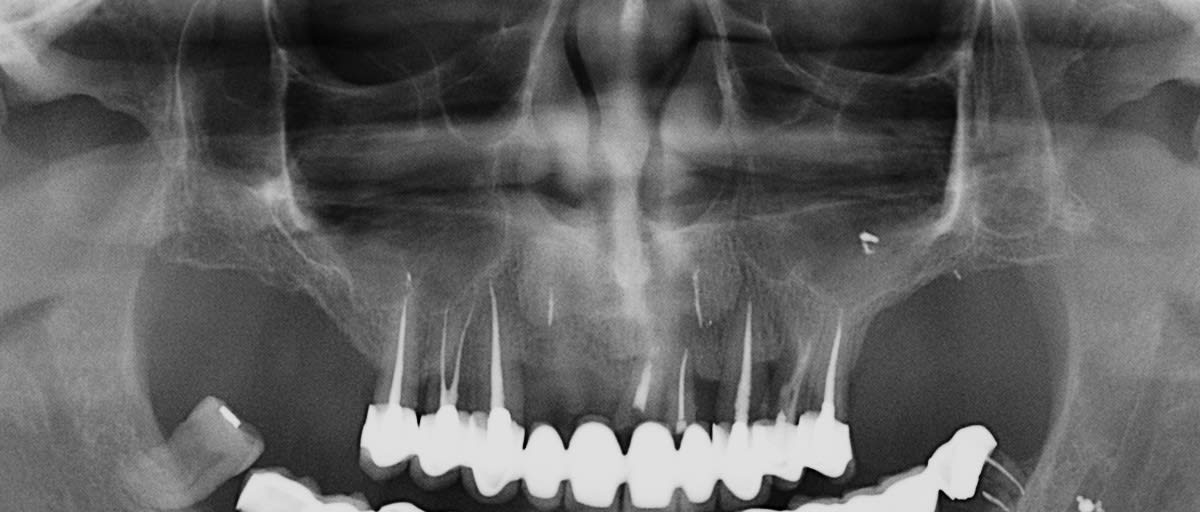

après avoir longtemps (depuis 1989) pratiqué des fenêtres latérales, je ne fais pratiquement que des summers (exemple ci dessous) en laissant du temps à la cicatrisation et jusqu'à présent pas de soucis particulier, et avant d'aller "bricoler" dans un sinus pour retirer du biooss (que je n'aime pas du tout) et/ou du tissus de "granulation", je prends le temps, et si l'implant est stable je ne me pose pas de question.

Ceci étant libre à chacun de pratiquer autrement

et comme tu peux le constater rien de "magique" ni dans la chir, ni pour la prothèse, très "bof" mais pas de problèmes pour le moment.